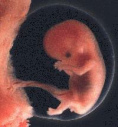

Sogar Feten [Föten] und Säuglinge sind in Leber und Nieren

bzw. in Gehirn und Nieren als Folge von Amalgamfüllungen

der Mutter bereits quecksilberbelastet (Drasch et al.

1994). Das Ausmass dieser fetalen bzw. frühkindlichen

amalgambedingten Quecksilberbelastung ist gravierend:

Babys (im Alter von 11 - 50 Wochen) von Müttern mit mehr

als 10 Amalgamfüllungen wiesen - in Korrelation mit dem

Amalgamstatus der Mütter - Werte von bis zu

2.543,8 µg Hg / kg

Nierengewebe

(Feuchtgewicht, so auch bei den folgenden Gewichtsangaben)

auf. Diese amalgambedingte Quecksilber-Konzentration liegt

Babys (11 - 50 Wochen) von Müttern mit 0 - lediglich 2

Amalgamfüllungen wiesen in der Studie von Drasch et al.

(1994) einen Spitzenwert von 75,9 µg Hg / kg Nierengewebe

(S.70)

auf. Mit Zunahme der Zahl der Amalgamfüllungen der Mütter

auf über 10 steigt der Quecksilbergehalt (Spitzenwert) in

den Nieren von Baby also auf mehr als das 30fache.